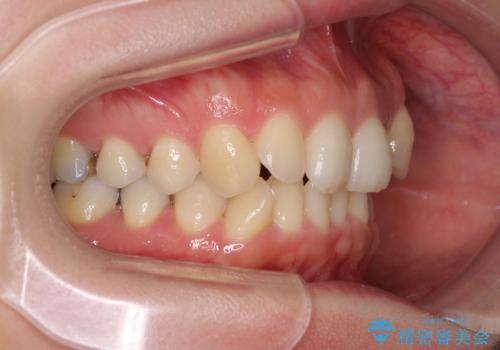

1日22時間の装着時間を守ってくださったので、比較的早く治療を終える予定でしたが、各国での入国制限が厳しくなり、帰国のタイミングに合わせてのんびりと治療を進めることとなってしまい、やや長期間の治療となりました。